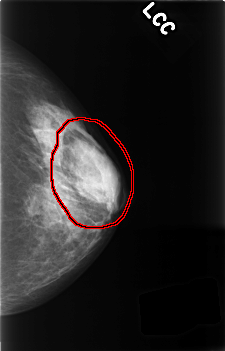

FILE: C_0430_1.LEFT_CC.OVERLAY

TOTAL_ABNORMALITIES 1

ABNORMALITY 1

LESION_TYPE MASS SHAPE OVAL MARGINS MICROLOBULATED

ASSESSMENT 3

SUBTLETY 5

PATHOLOGY BENIGN_WITHOUT_CALLBACK

TOTAL_OUTLINES 1

BOUNDARY